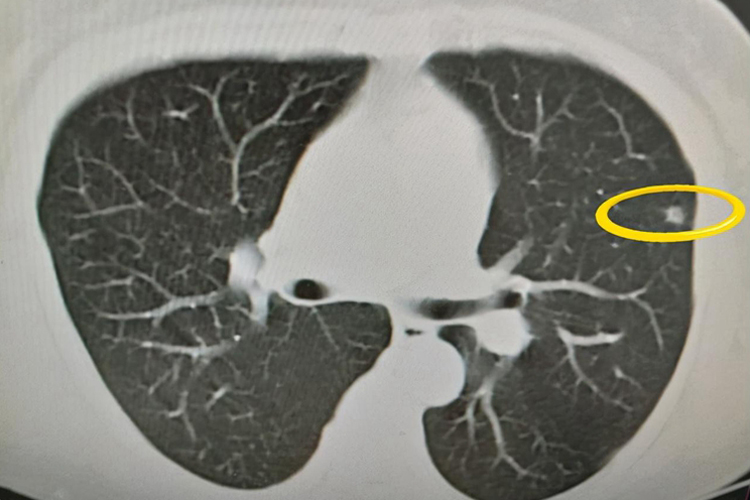

- 实性结节指的是肺部某区域肺组织密度增高,边缘可能尖锐或模糊,形态多为圆形或椭圆形。这种结节常见于肺部炎症、肿瘤、出血等情况。

- 磨玻璃结节则表现为肺部影像中的点状或片状磨玻璃样改变,其密度相对较低,但轮廓清晰。这种结节常见于肺炎、肺结核、肺泡蛋白质沉着症等多种疾病。

- 双肺多发实性及磨玻璃结节可能是良性病变,如肺炎、肺纤维化等,经过治疗可消失。然而,也可能是恶性病变的征兆,如肺癌,特别是当结节直径较大、形态不规则或伴有空泡征、分叶征时,应高度警惕。